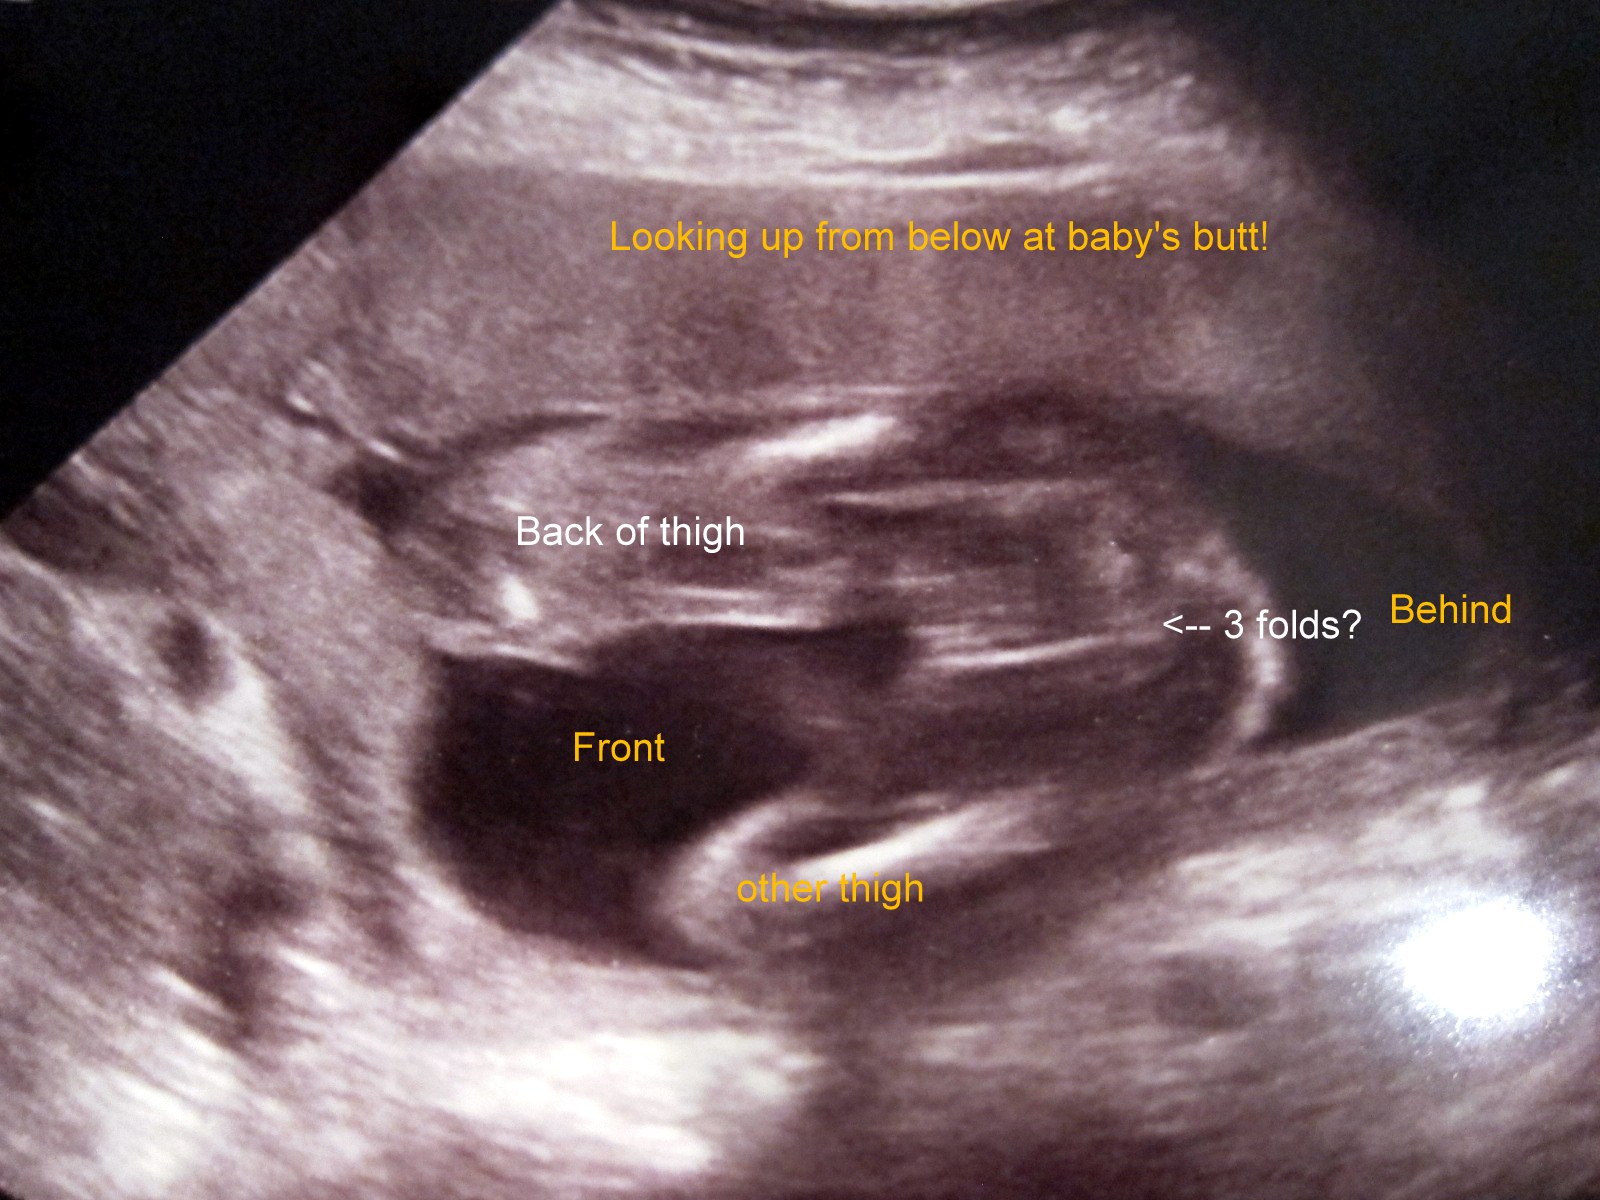

Baby didn't want to open her legs up, ultrasound tech was thinking girl, couldn't find anything else but not 100% sure. Going to go get another scan in a week.

Thoughts? Thank you!

Attachment 7502